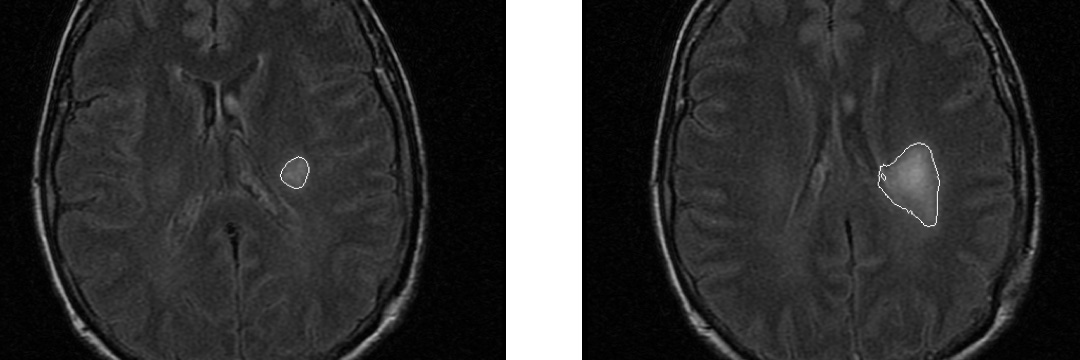

Les champs d'expertise numérique de l'équipe reposent sur les champs suivants : intelligence artificielle, image, analyse exploratoire de données, observabilité des données, analyse multiéchelle, morphologie mathématique, topologie discrète, filtrage spatio-fréquentiel, analyse dynamique, classification, décision, mesure de similarité, détection de changements, modélisation statistique.

Les champs d'expertise clinique de l'équipe reposent sur les modalités suivantes : imagerie par résonance magnétique (IRM), scanner (TDM), artériographie, imagerie nucléaire (TEP, TEMP), électroencéphalographie (EEG), échographie, imagerie préclinique (synchrotron). Les domaines cliniques privilégiés sont la néonatologie, la cancérologie, la neurologie, la radiologie, l'endocrinologie, l'urologie, l'histopathologie.